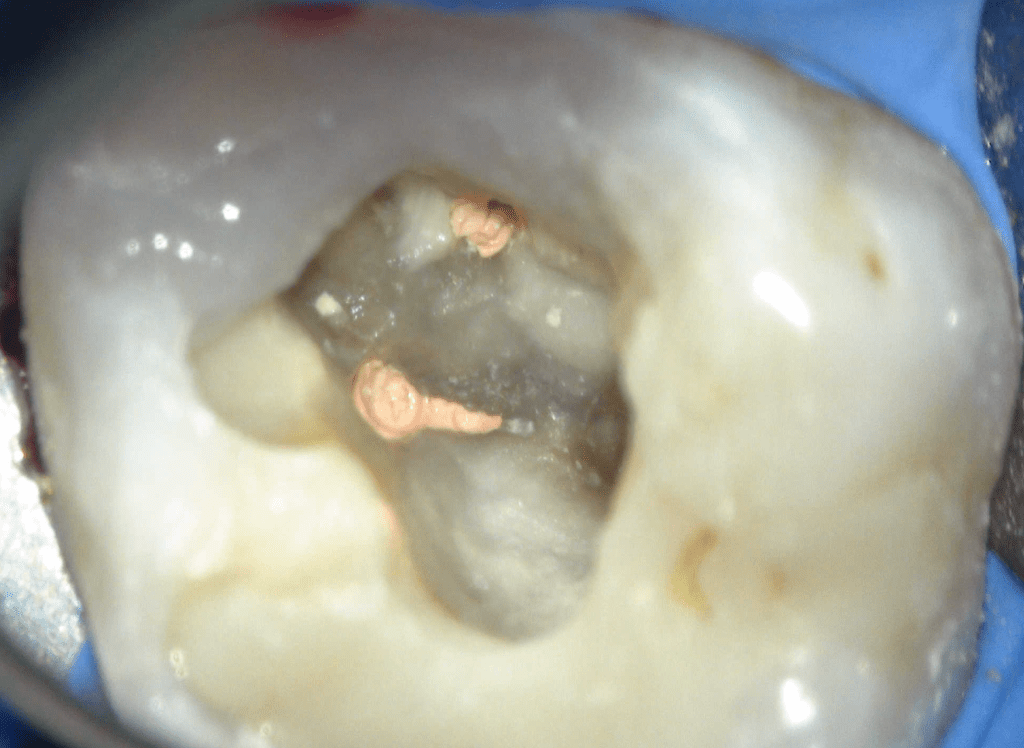

Reconstrucción preendodóntica

Reco preendo + 4 conductos molar superior